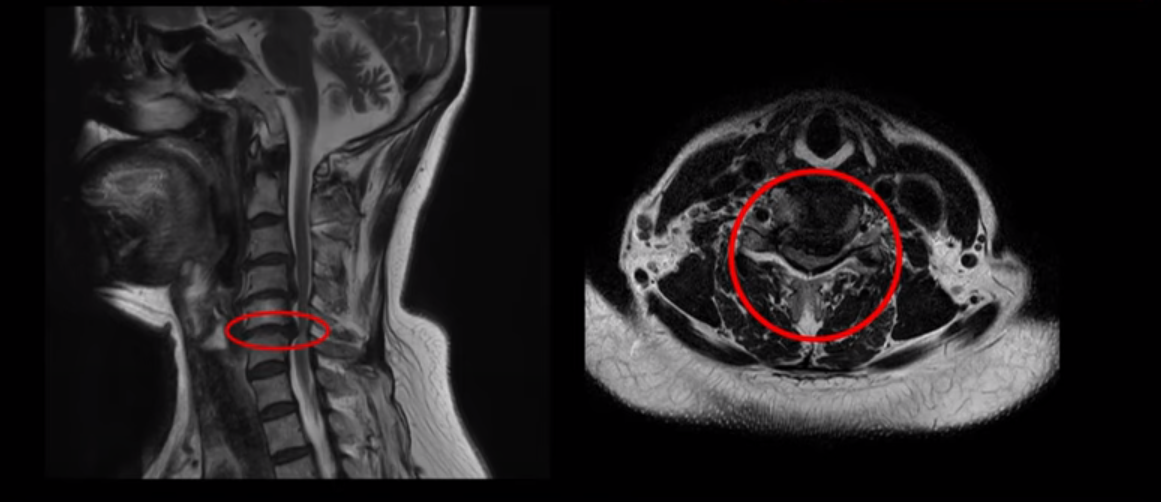

양손 마비와 보행 시 균형을 못 잡고 비틀거리는 환자분의 MRI 상태 및 증상은?

이 환자분은 목디스크 5번, 6번에 심한 디스크로 인해 경추척수증이 발생한 환자입니다. MRI에 보시는 것처럼 디스크가 심하게 밀려나와 이로 인해 척수신경이 눌려 신경손상이 하얗게 보입니다.

환자분의 증상은 양쪽 손, 특히 손바닥에 다 마비가 오고 다리 힘이 빠져 균형을 잡지 못해 비틀거리며 잘 걷지 못하셨습니다. 이는 경추척수증의 전형적인 증상입니다. 대학병원에서도 별다른 구체적인 설명 없이 무조건 수술해야 한다는 말을 듣고 저희 모커리한방병원에 내원하셨습니다.

경추척수증은 뇌에서부터 나와 목을 통해 전신으로 내려가는 중추신경인 척수가 목디스크, 골화된 후종인대, 경추 협착으로 인해 심하게 눌려 손상이 생기는 질환입니다. 그렇기 때문에 감각기능, 운동기능 저하 등의 증상이 발생합니다. 뿐만 아니라 양손, 팔 등에 통증은 물론 저리는 증상이 나타나고 손의 움직임이 둔해지며 다리 근력도 약화돼 힘이 빠집니다. 또한 균형을 잘 잡지 못해 걸음을 휘청거리는 등 보행장애 증상이 나타나기도 합니다.